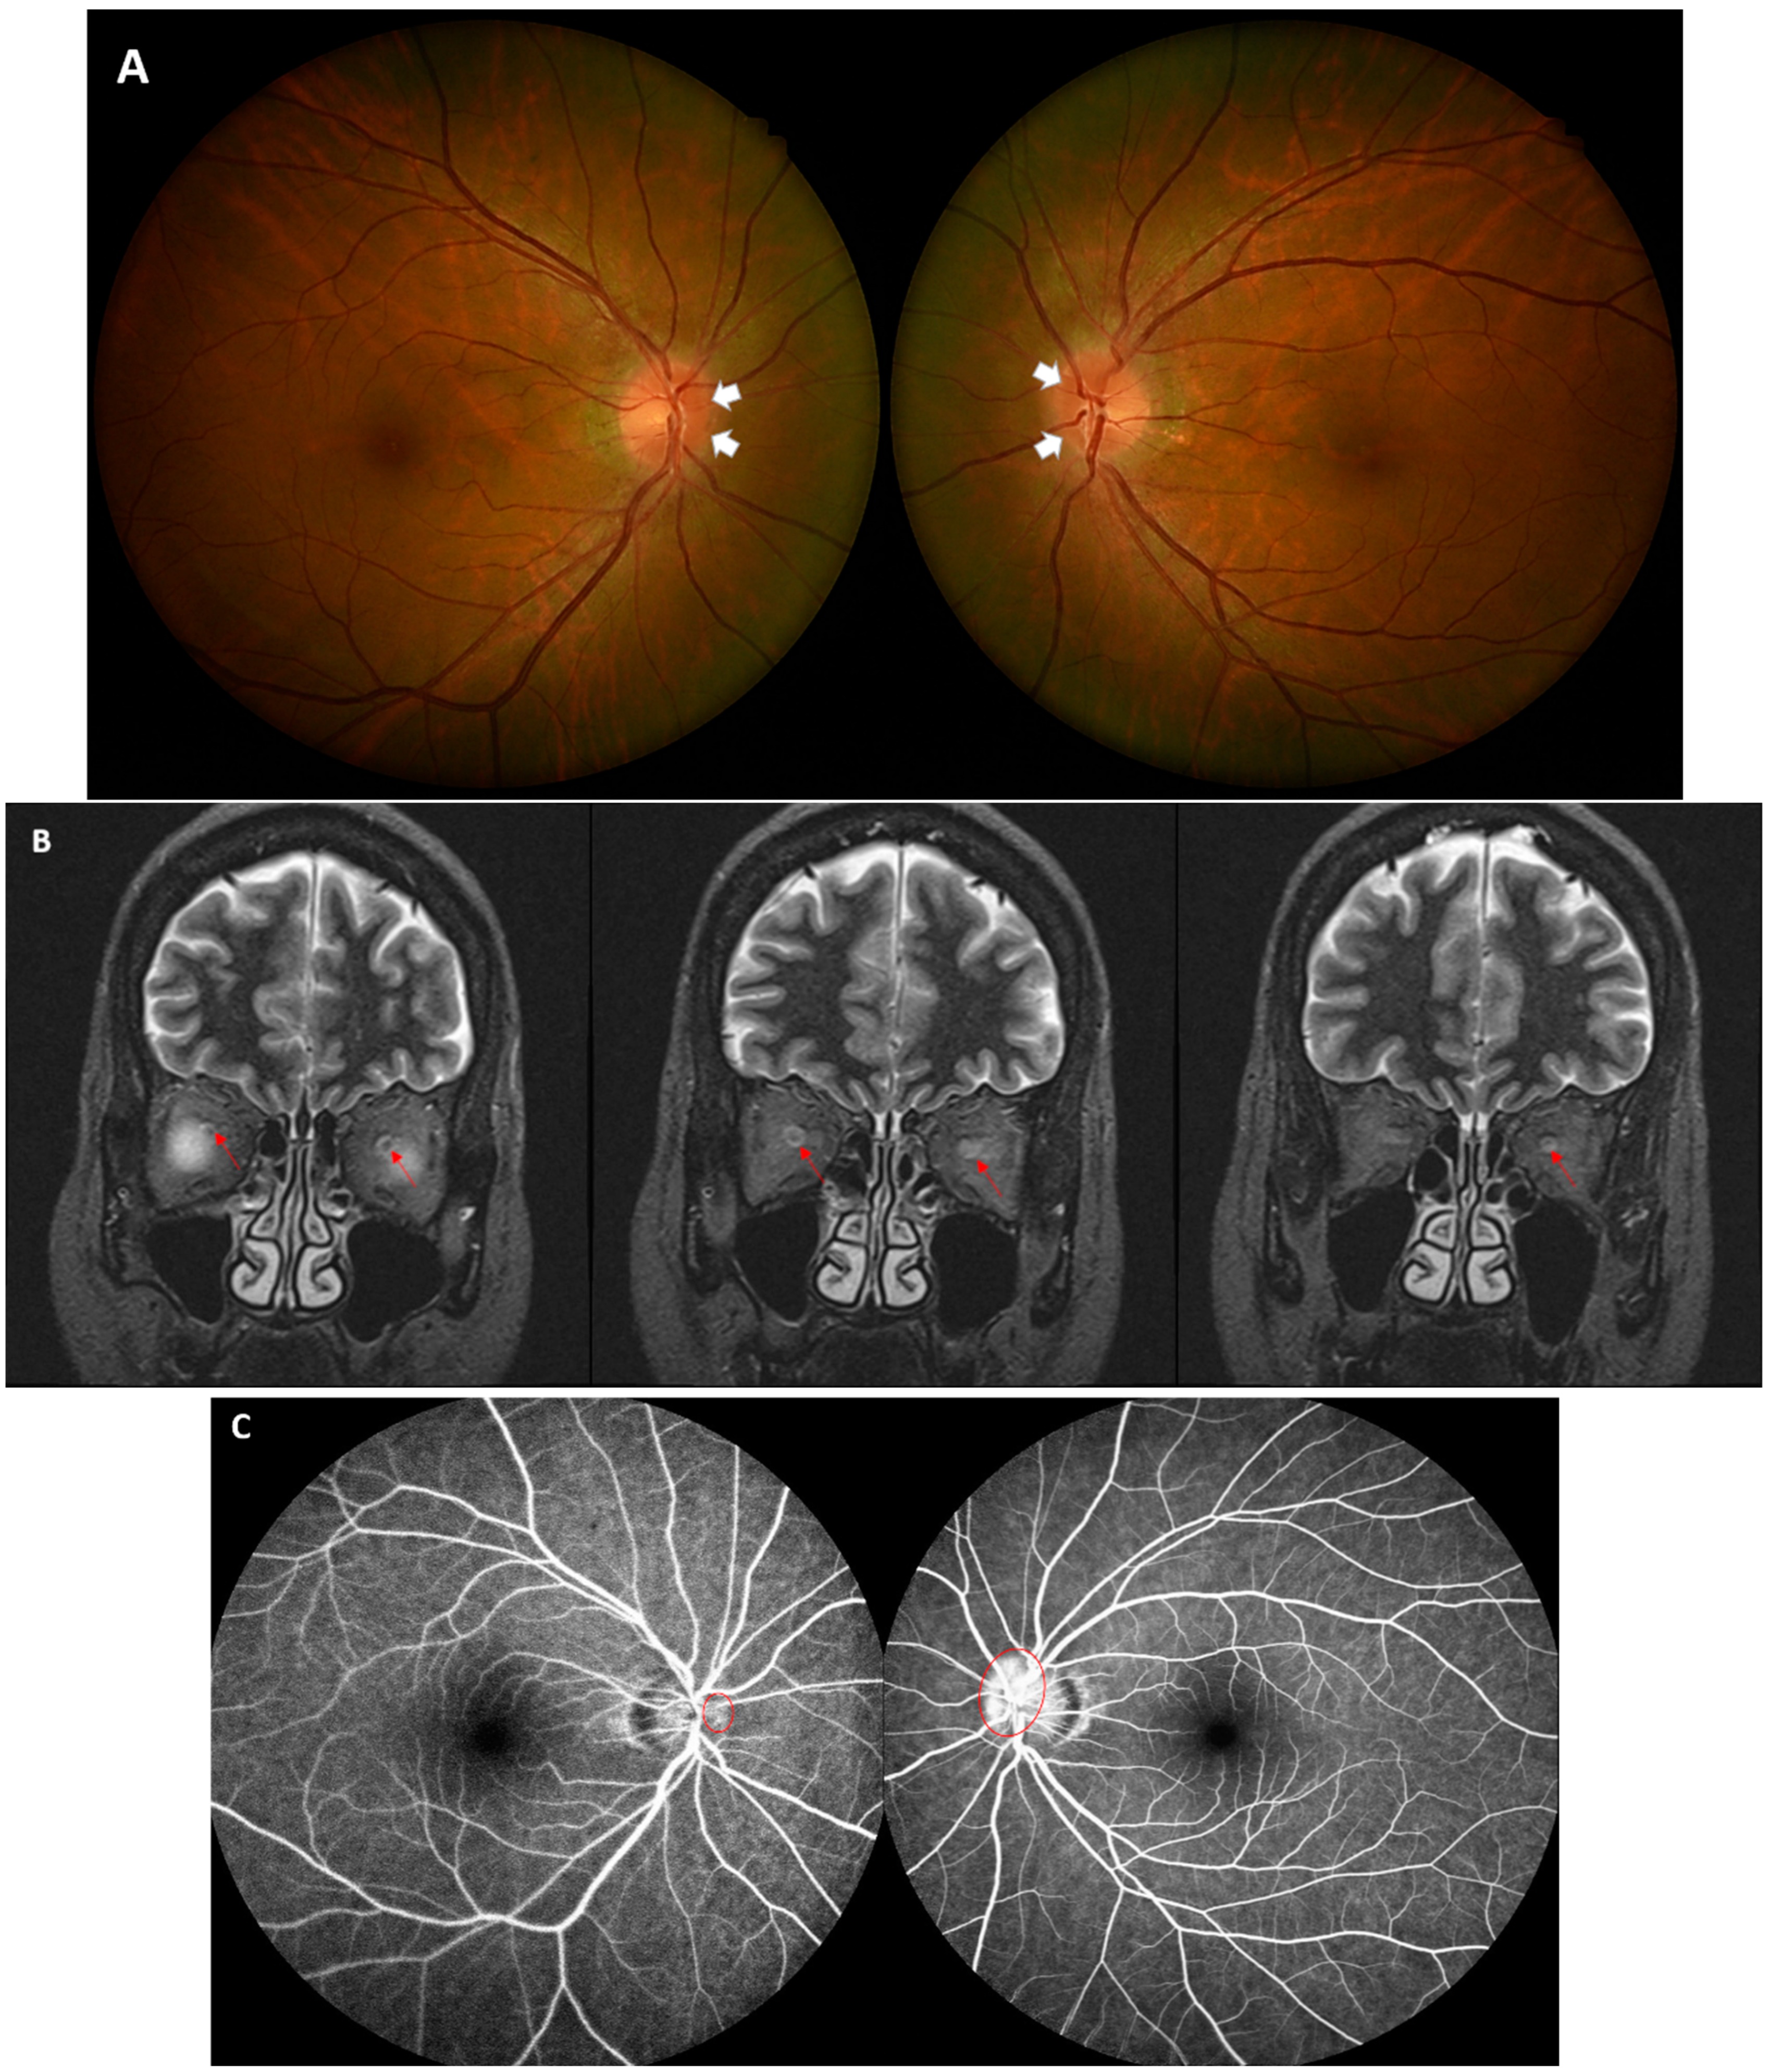

2. Case Presentation